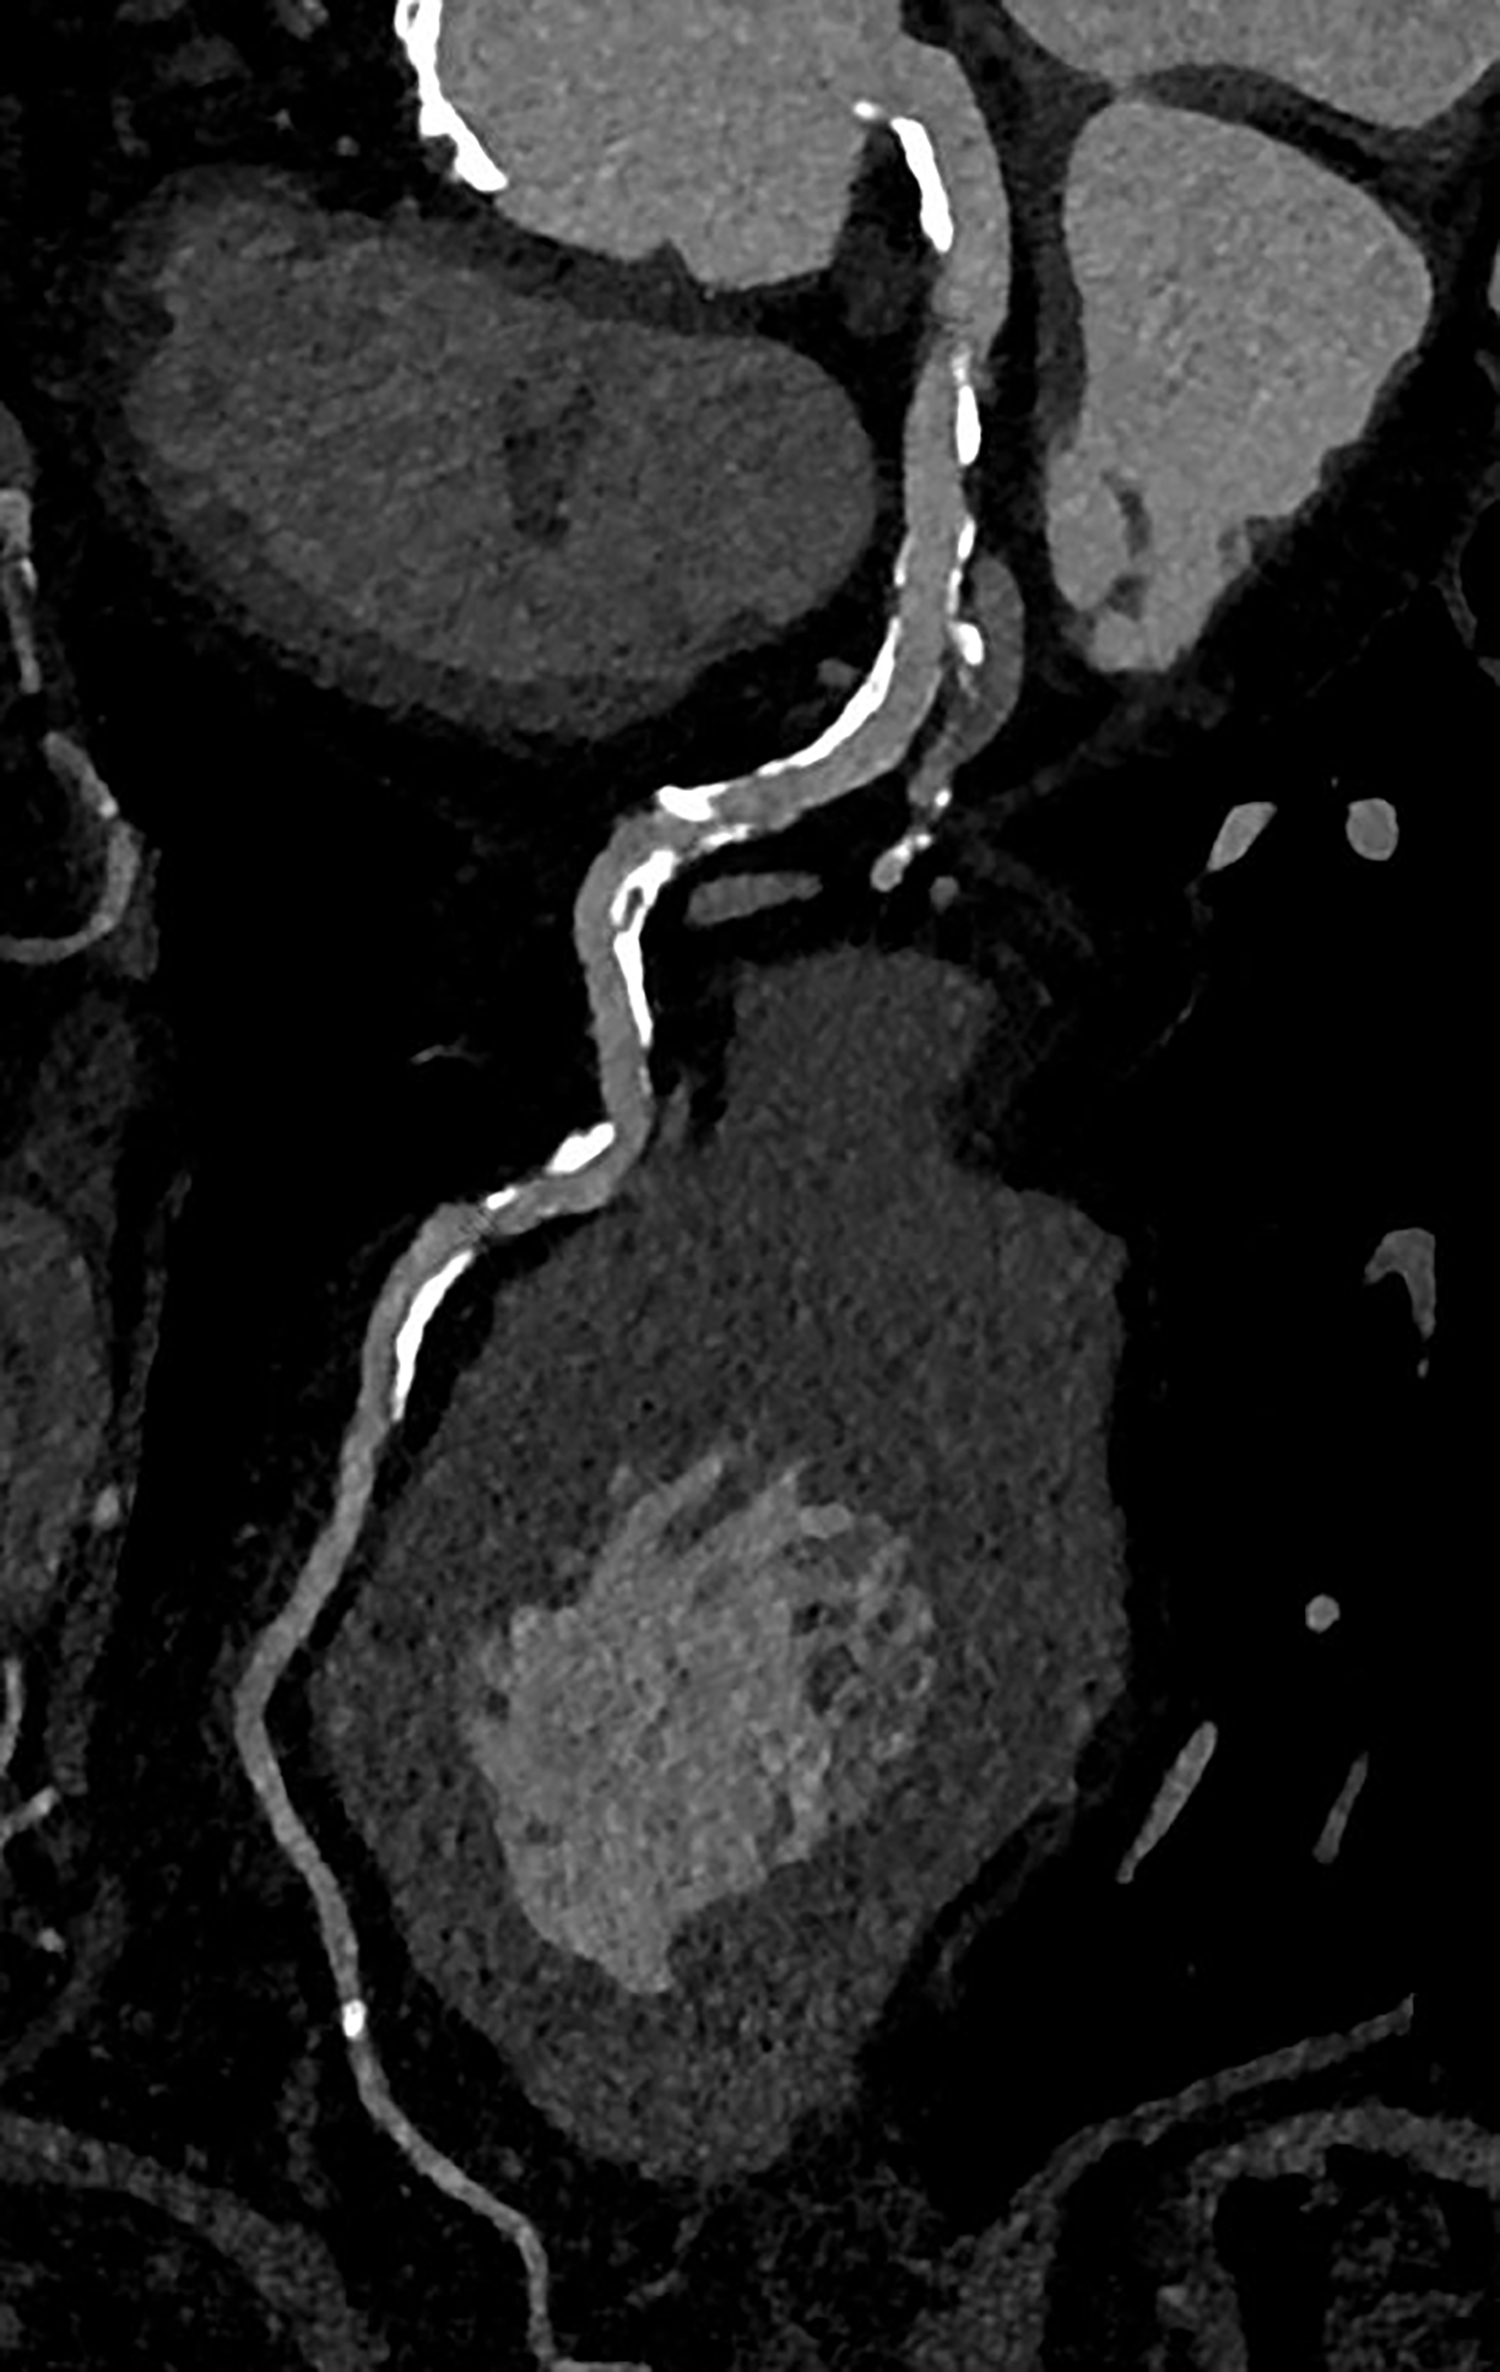

Bildunterschrift: Photon-Counting CT des Herzen eines 87-jährigen Patienten. Trotz sehr schwerer Verkalkungen an den Gefäßwänden (in der 3D-Aufnahme zu sehen), gelingt eine diagnostische Darstellung, die zeigt, dass die Gefäße nicht verstopft sind. Ein Kathetereingriff ist in diesem Fall nicht nötig.

Die koronare CT-Angiographie eignet sich besonders gut zum Ausschluss einer koronaren Herzerkrankung bei Patient*innen mit niedrigem oder mittlerem Risiko für Veränderungen der Herzkranzgefäße. Bei Personen mit hohem Risiko gestaltete sich dies bislang aufgrund von häufig auftretenden koronaren Verkalkungen und Stents jedoch schwierig. Muhammad Taha Hagar, Erstautor der Studie und Arzt der Klinik für Diagnostische und Interventionelle Radiologie am Universitätsklinikum Freiburg erklärt: „In klassischen CT-Bildern erscheinen Verkalkungen der Herzkranzgefäße oft größer als sie tatsächlich sind. Dieser Effekt ist umso stärker, je größer die Verkalkung ist.“ Dadurch konnte es bislang zu einer Überbewertung von Verengungen und Plaques und in der Folge zu einer Überbehandlung kommen. Darum wurden diese Personen bislang schnell in den Herzkatheter überweisen oder in der Magnetresonanztomografie untersucht.

In der von Hagar und Kolleg*innen durchgeführten Studie wurden 68 Proband*innen mittels Photon-Counting-CT und einer invasiven Koronarangiografie als Referenzstandard untersucht. Die Patient*innen litten alle unter einer schweren Aortenklappenstenose, einer gängigen, aber ernsthaften Herzerkrankung, die den Blutfluss vom Herzen zur Aorta reduziert oder blockiert. Die Photon-Counting-CT-Untersuchung zeigte sich sehr genau in der Erkennung oder dem Ausschluss der koronaren Herzerkrankung. Auch wurde die Bildqualität in fast 80 Prozent als gut oder hervorragend bewertet.